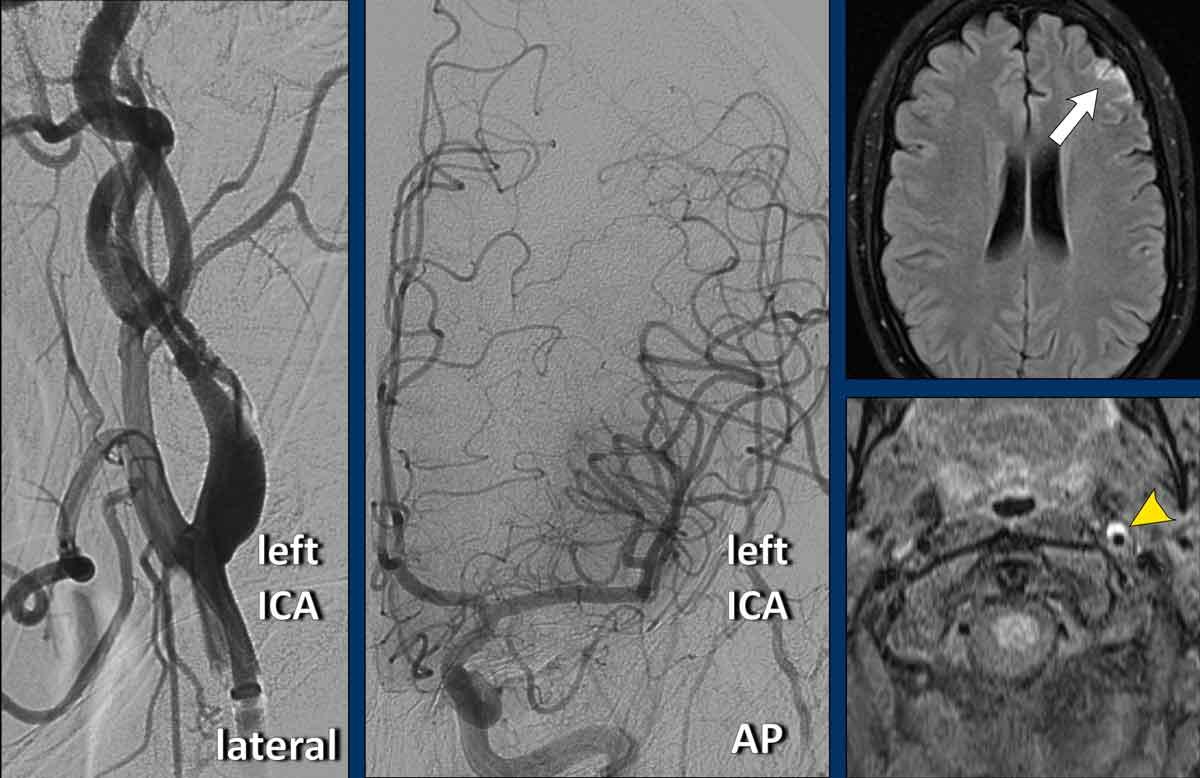

Ca lâm sàng

Một phụ nữ 35 tuổi nhập cấp cứu với triệu chứng rối loạn ngôn ngữ và liệt nửa tay phải.

Chụp CT sọ não không tiêm thuốc (NECT) không cho thấy dấu hiệu chảy máu hay nhồi máu.

Trên CT có tiêm thuốc cản quang (CECT), các mạch máu nội sọ ngấm thuốc bình thường, nghĩa là không có tắc nghẽn nội sọ.

Trong vòng 20 phút, bệnh nhân được điều trị tiêu sợi huyết đường tĩnh mạch (IV), dẫn đến phục hồi một phần.

Tuy nhiên, một giờ sau, tình trạng xấu đi với liệt nửa người bên phải và mất ngôn ngữ.

Thang điểm NIHSS là 27.

Sau đó, bệnh nhân được chuyển đến trung tâm can thiệp.

CTA vùng cổ cho thấy hình ảnh đặc trưng dạng ngọn lửa ở đoạn gần ICA, gợi ý bóc tách động mạch.

Hình ảnh lát cắt ngang cho thấy ICA trái giãn rộng với lòng mạch bị chèn ép lệch tâm.

Tóm lại, đây là trường hợp phụ nữ 35 tuổi với đột quỵ diện rộng (NIHSS = 27), tắc nghẽn động mạch cảnh do bóc tách, nhưng không có tắc nghẽn nội sọ.

Chụp mạch số hóa xóa nền (DSA) ICA trái xác nhận bóc tách (đầu mũi tên) qua hình ảnh cấu hình dạng ngọn lửa ở đoạn gần ICA.

Tiếp theo, DSA của ICA phải và động mạch đốt sống trái được thực hiện.

Chụp mạch ICA phải cho thấy vắng mặt động mạch thông trước (Acom) do thuốc cản quang không đi từ phải sang trái. Ngoài ra, bơm thuốc cản quang vào động mạch đốt sống trái cho thấy vắng mặt động mạch thông sau (Pcom).

Đây là bằng chứng xác nhận chẩn đoán “Động mạch cảnh bị cô lập”.

Giảm tưới máu vùng động mạch não trước và động mạch não giữa (toàn bộ là vùng tranh tối tranh sáng, không có lõi nhồi máu trên hình ảnh CBV – không hiển thị)

Vậy giải thích thế nào về việc động mạch não giữa trái vẫn ngấm thuốc cản quang trong khi ICA trái bị tắc và không có tuần hoàn bàng hệ qua đa giác Willis?

Giải thích là do có các nhánh bàng hệ nhỏ giữa động mạch cảnh ngoài (ECA) và ICA.

Lượng máu này đủ để làm đầy động mạch não giữa bằng thuốc cản quang, nhưng không đủ để tưới máu thích hợp cho bán cầu não trái.

Điều này được thể hiện rõ ràng trên hình ảnh tưới máu.

Trong quá trình can thiệp, lưu lượng máu được phục hồi do vạt nội mạc được tái định vị bởi thao tác của ống thông.

Đặt stent động mạch cảnh được cân nhắc nhưng không thực hiện.

Bệnh nhân được điều trị bằng Fraxiparine.

Sau 24 giờ, thang điểm NIHSS là 2 với chỉ còn mất ngôn ngữ nhẹ; sau 3 tháng, NIHSS giảm xuống 0.

MRI theo dõi sau một tháng cho thấy nhồi máu nhỏ thùy trán trái (mũi tên trắng).

ICA trái thông và còn lại hình ảnh tụ máu trong thành mạch với tăng tín hiệu trên chuỗi xung T1W (đầu mũi tên).